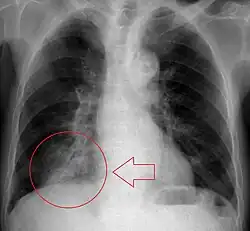

Da die Aspirationspneumonie ein weites Spektrum von aspirierter Flüssigkeit, Aspirationsmenge, Keimgehalt des Aspirats, Komorbidität des Patienten und betroffenem Abschnitt von Lunge und Bronchalbaum hat, ist auch das klinische Erscheinungsbild variabel.[4] Voraussetzung ist auf jeden Fall eine Makroaspiration, wobei die genaue Menge des notwendigen Aspirats unklar ist. Die Erstsymptomatik reicht von symptomlos bis zu lebensbedrohlicher Ateminsuffizienz. Der Kontakt des Aspirats mit den Bronchien kann einen Bronchospasmus, einen Asthmaanfall oder einen Dauerhusten auslösen. Die Veränderungen am Lungenparenchym treten typischerweise erst nach einigen Stunden oder Tagen auf. Die Lungenentzündung nach Aspiration ist schwer von einer anderen bakteriellen Infektion zu unterscheiden. Bei alten Patienten ist die Sterblichkeit einer Pneumonie nach Aspiration höher als ohne Aspiration.[5] Diese erhöhte Mortalität wurde auch bei ambulant erworbenen Pneumonien festgestellt. In der bildgebenden Diagnostik (Röntgen-Thorax, CT des Thorax) sieht man Infiltrate in den unteren Lungenabschnitten. Bei Rückenlage sind die basalen Segmente des Unterlappens betroffen. Bei aufrechter Haltung sind die oberen Unterlappensegmente oder die hinteren Oberlappensegmente am häufigsten infiltriert. Ein normales Röntgenbild zeigt in bis zu 60 % keine Zeichen der Aspiration. Im CT ist die Diagnose der Aspiration besser.[6] Die höchste diagnostische Genauigkeit hat das HRCT (CT mit hoher Auflösung).